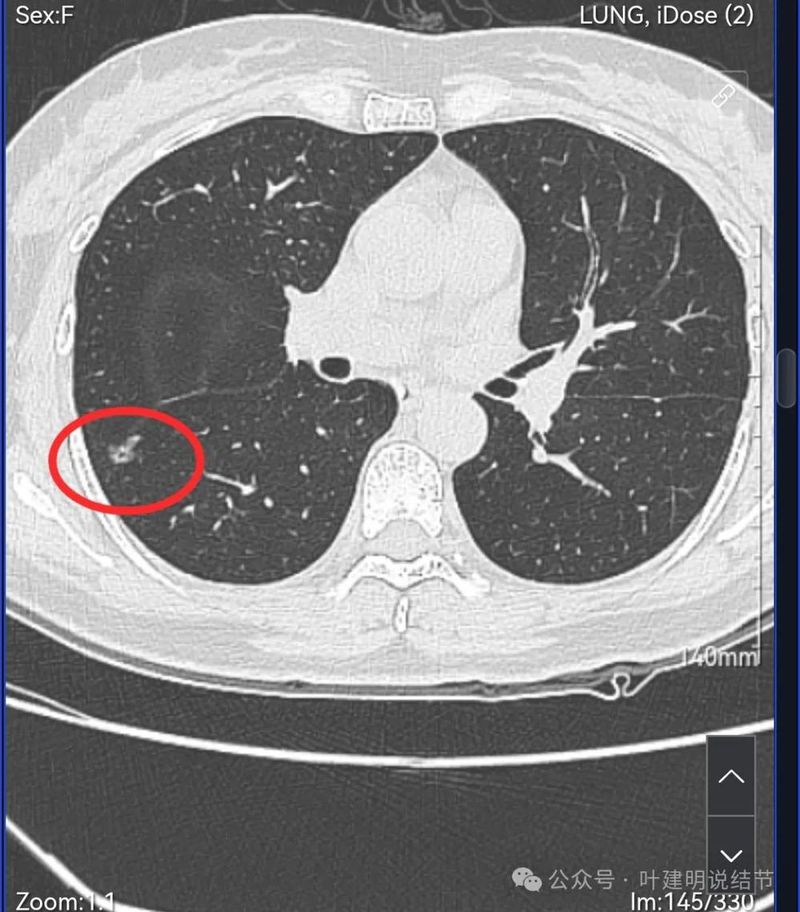

病灶3:右下叶混合密度结节,轮廓清,紧贴叶裂,伴有叶间胸膜牵拉,内部密度显杂乱,表面有分叶。

此灶分叶明显,灶内有小空泡征,有血管穿行,整体轮廓与边界清楚。

病灶出现,紧贴叶间裂。

轮廓清楚,叶间胸膜牵拉。

右肺多发磨玻璃结节,红色的是主病灶,密度不纯,贴着叶间裂,分叶明显,考虑至少微浸润性腺癌,也可能是浸润性腺癌贴壁为主型,不能继续随访,建议手术切除,可以单孔胸腔镜下局部楔形切除。黄色的也是磨玻璃,不典型增生或者肺泡上皮增生可能性大,蓝色的肺泡上皮增生可能性大。这两处风险还低,但如果主病灶需要处理,也可以考虑同期切除。意见供参考!